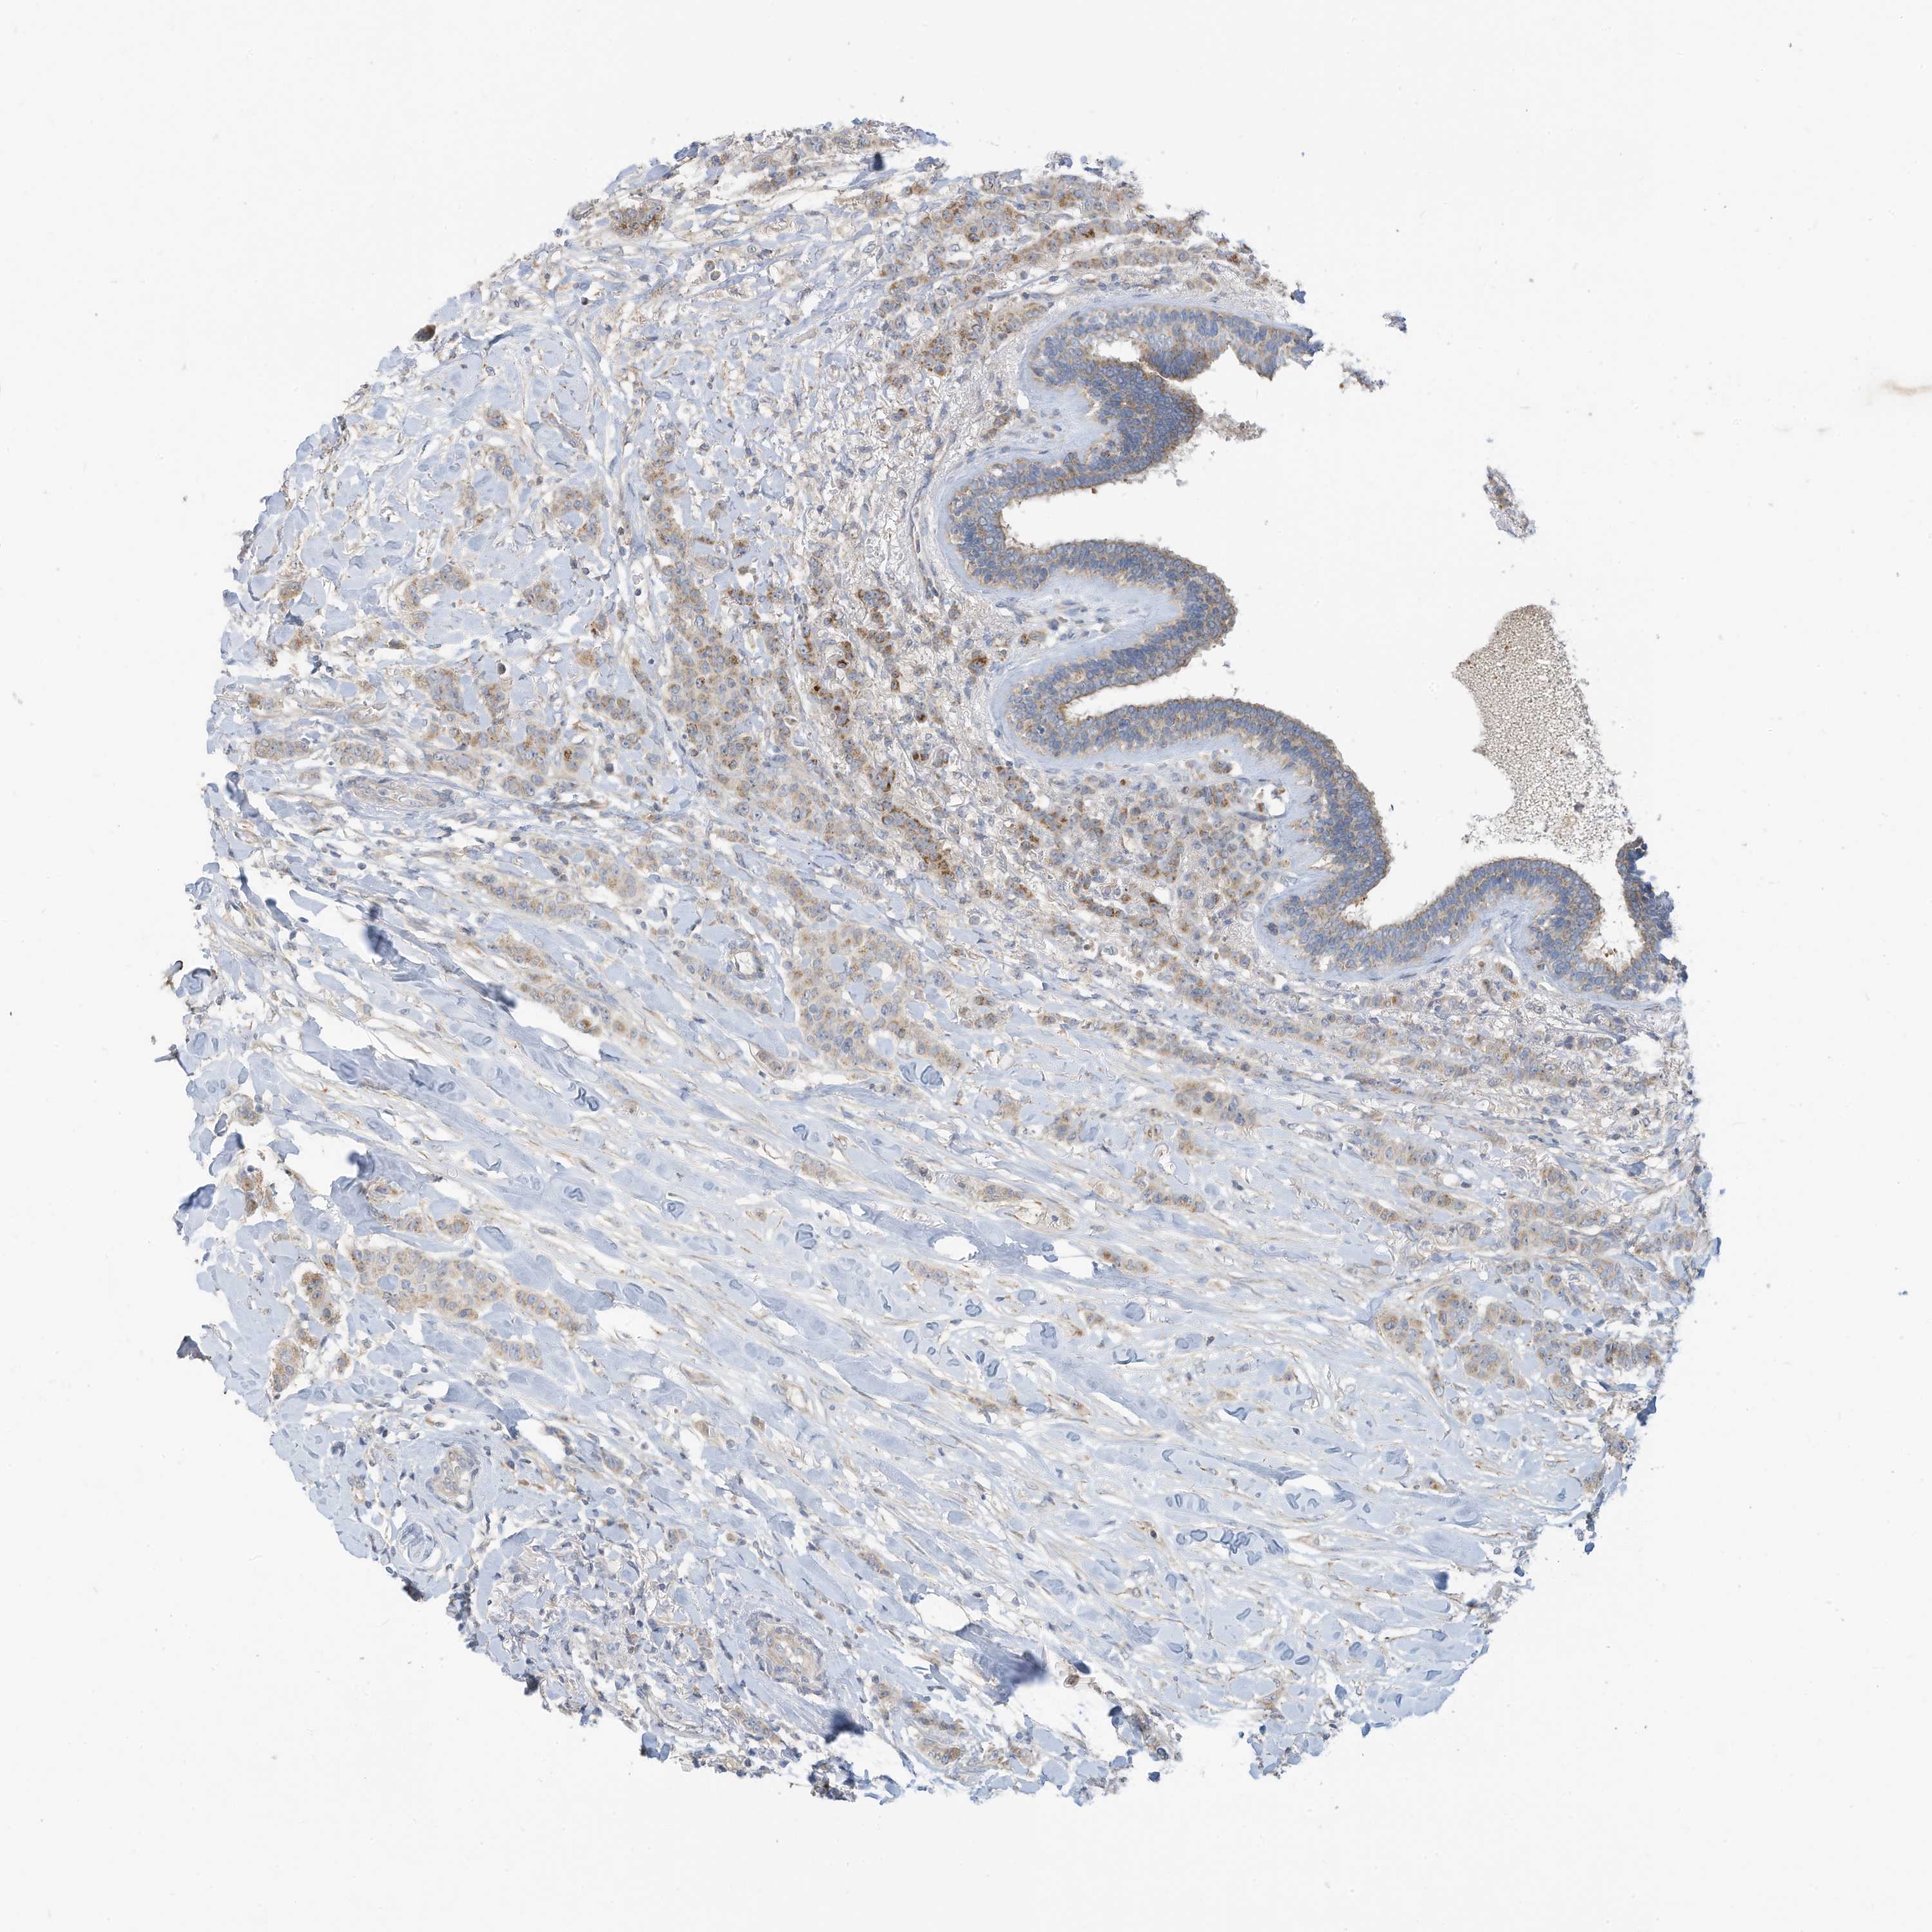

CANCER BREAST CANCER Show tissue menu

BRCA TCGA BRCA VALIDATION PROTEIN EXPRESSION